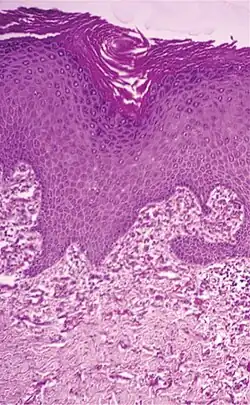

| Actinic elastosis (most common, also called solar elastosis) |

Elastin replacing collagen fibers of the papillary dermis and reticular dermis |

|